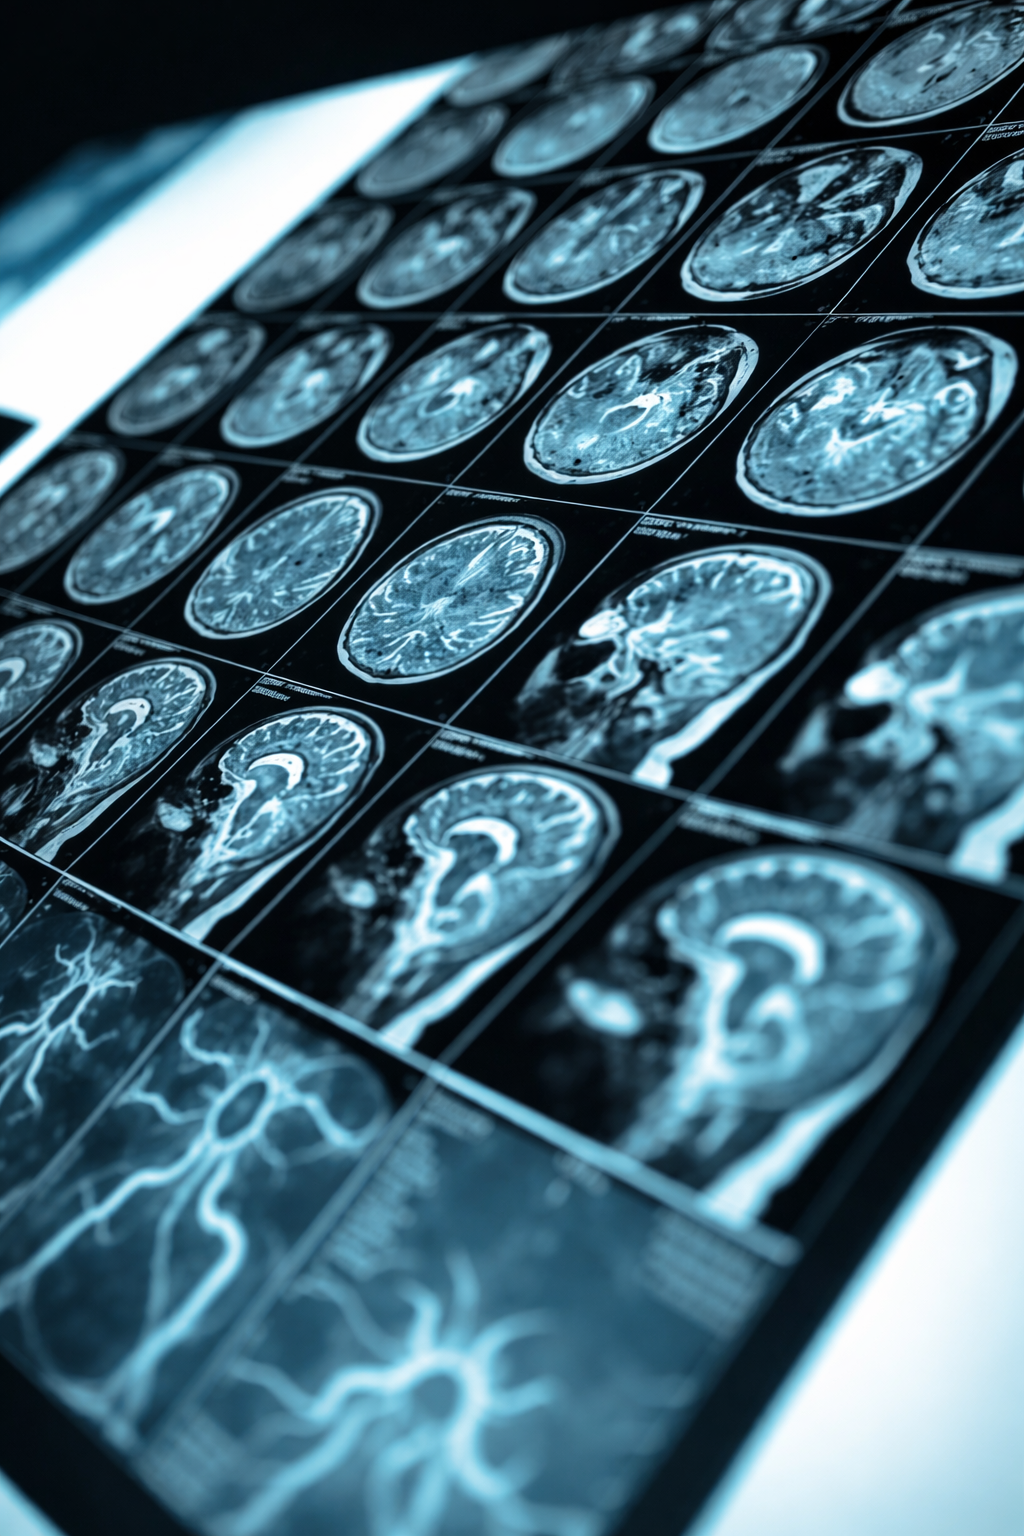

Atiendo pacientes con dolor de columna, hernia de disco, ciática, patología cerebrovascular y tumores del sistema nervioso, con evaluación especializada y enfoque individualizado.

Experiencia en el tratamiento de aneurismas cerebrales, tumores del sistema nervioso central, patología vascular cerebral y cirugía mínimamente invasiva de columna, integrando tecnología avanzada y precisión microquirúrgica.